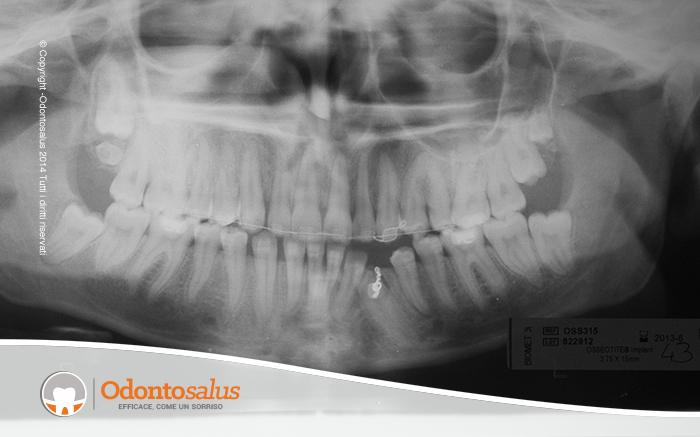

Il paziente presenta l’elemento 33 incluso.

Come mostrato dalla presenza di una catenella nella radiografia pre cure, è stato eseguito un trattamento ortodontico per riportare l’elemento incluso in arcata. In questo caso, considerata la presenza di alcuni fattori quali l’età, la densità ossea e la posizione del dente, può accadere che il dente non risenta di alcuna trazione, restando fermo nella sua posizione.